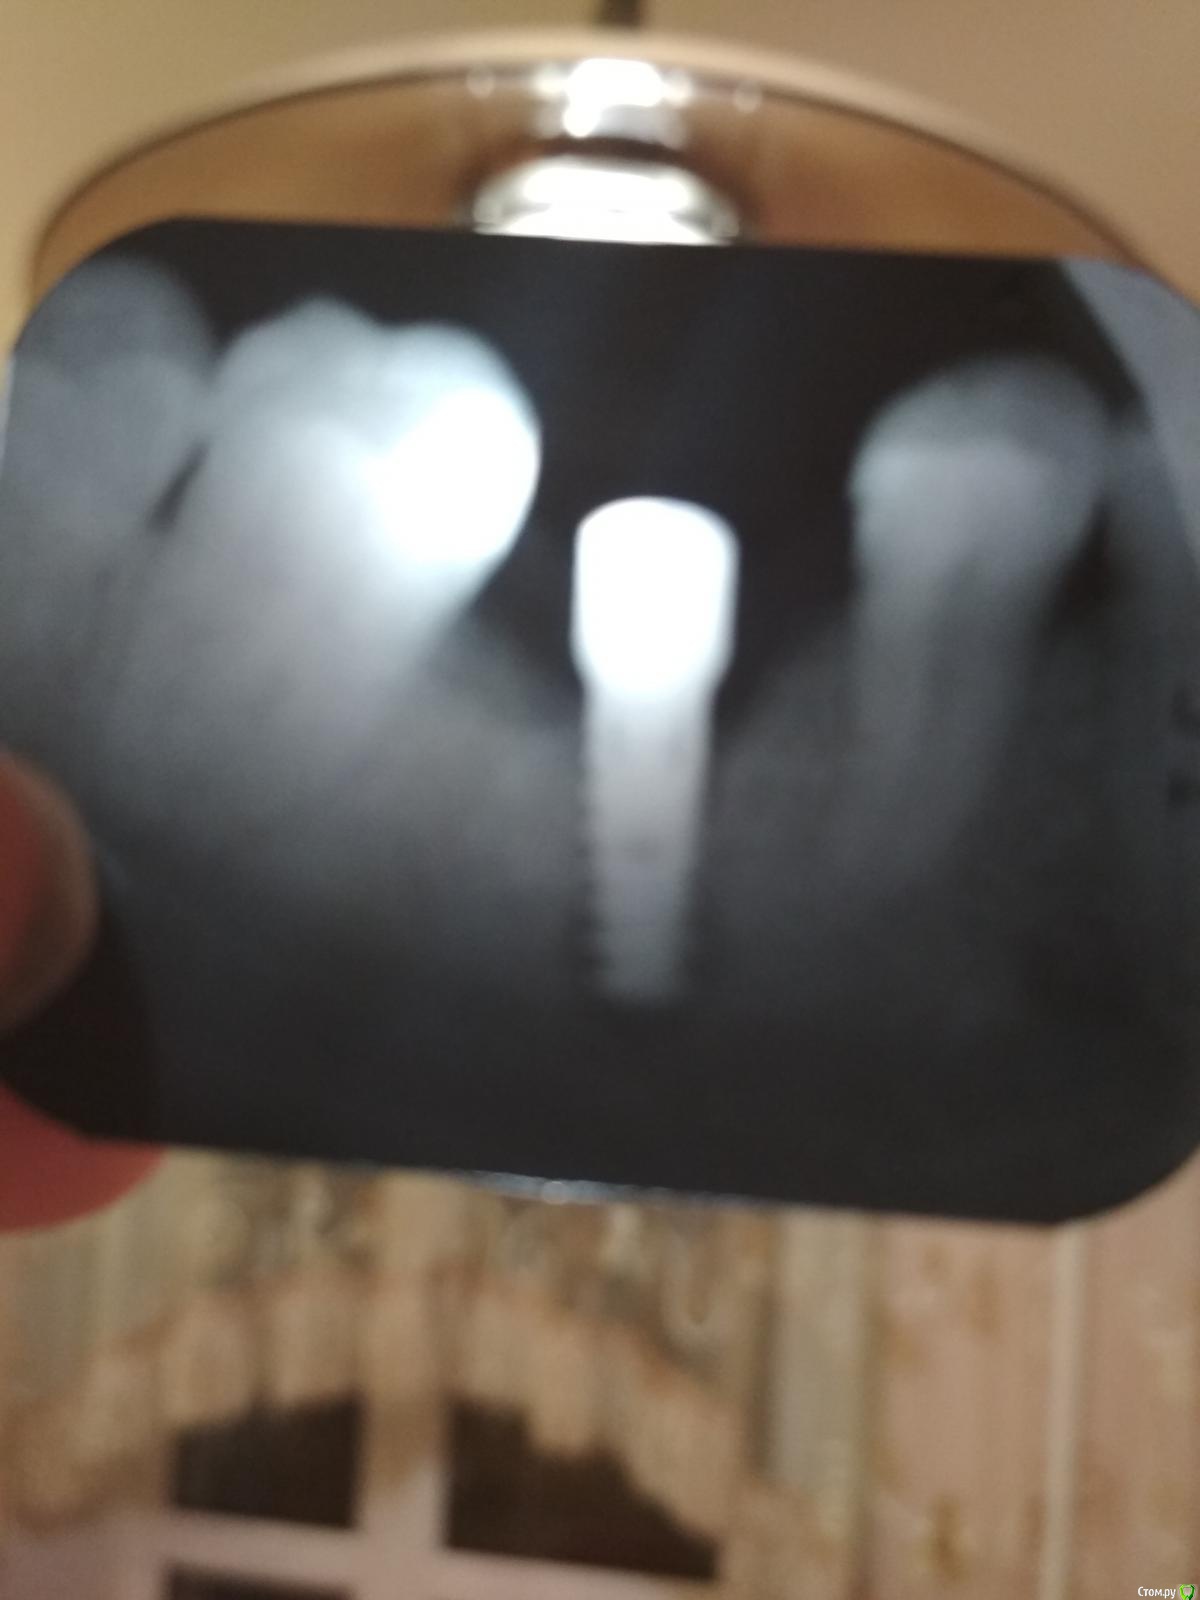

Nata_3679 Опубликовано 13 ноября, 2017 Поделиться Опубликовано 13 ноября, 2017 (изменено) Добрый день, подскажите, что с имплантом, смущает темное пятно снизу, имплантация проведена 2 2 сентября. СпасибоЖалоб у меня нет, нагрузку на имплант пока не даю. Две недели назад врач поставил формирователь десны, был заглушечный свищ. Изменено 13 ноября, 2017 пользователем Nata_3679 Ссылка на комментарий

Большой Зеленый Опубликовано 14 ноября, 2017 Поделиться Опубликовано 14 ноября, 2017 Верхушечный периимплантит)))Это менталис наслоился ...Новый снимок прояснит Ссылка на комментарий

Nata_3679 Опубликовано 14 ноября, 2017 Автор Поделиться Опубликовано 14 ноября, 2017 Сегодня была на приеме, врач сказал, что ситуация необычная, снимок плохой,прямое показание к извлечению, а на очным осмотром он остался удовлетворен. Следующий прием через 2 недели, на котором будет принято окончательное решение Ссылка на комментарий